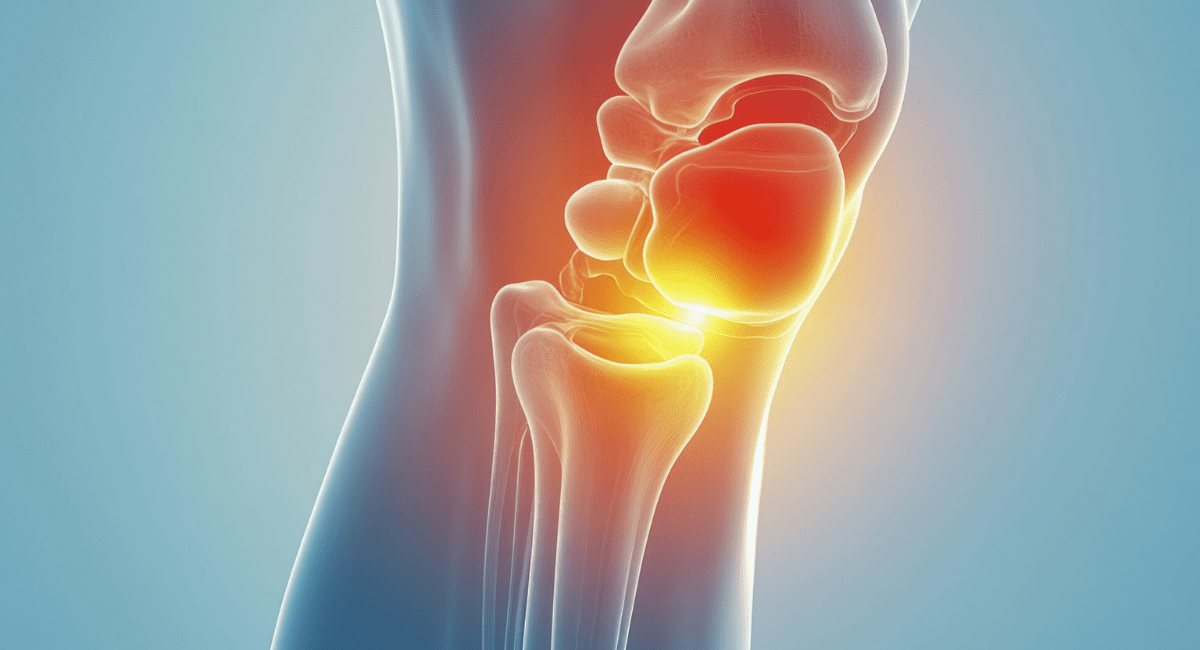

What are My Options for Physiotherapy Care

I discussed the presentation with the patient to ensure he had a good understanding of the problem and the likely outcome of treatment. I treated to the weak and painful tendons with soft tissue mobilisation, massage, stretching, a graduated strengthening programme. His strengthening programmers consisted of to the series of weight and theraband work, as well as using a Powerball. as these generally require stronger evidence.

The muscles in his forearms were wasted and his shoulders were protracted. There were no signs of bone abnormality, nerve or significant soft a tissue injury. He had good movement, but his strength was reduced on both sides on grip and wrist strength in particular. His shoulder were also slightly weak in the rotator cuff. He had pain on palpation of his forearms generally, particularly pronator teres.